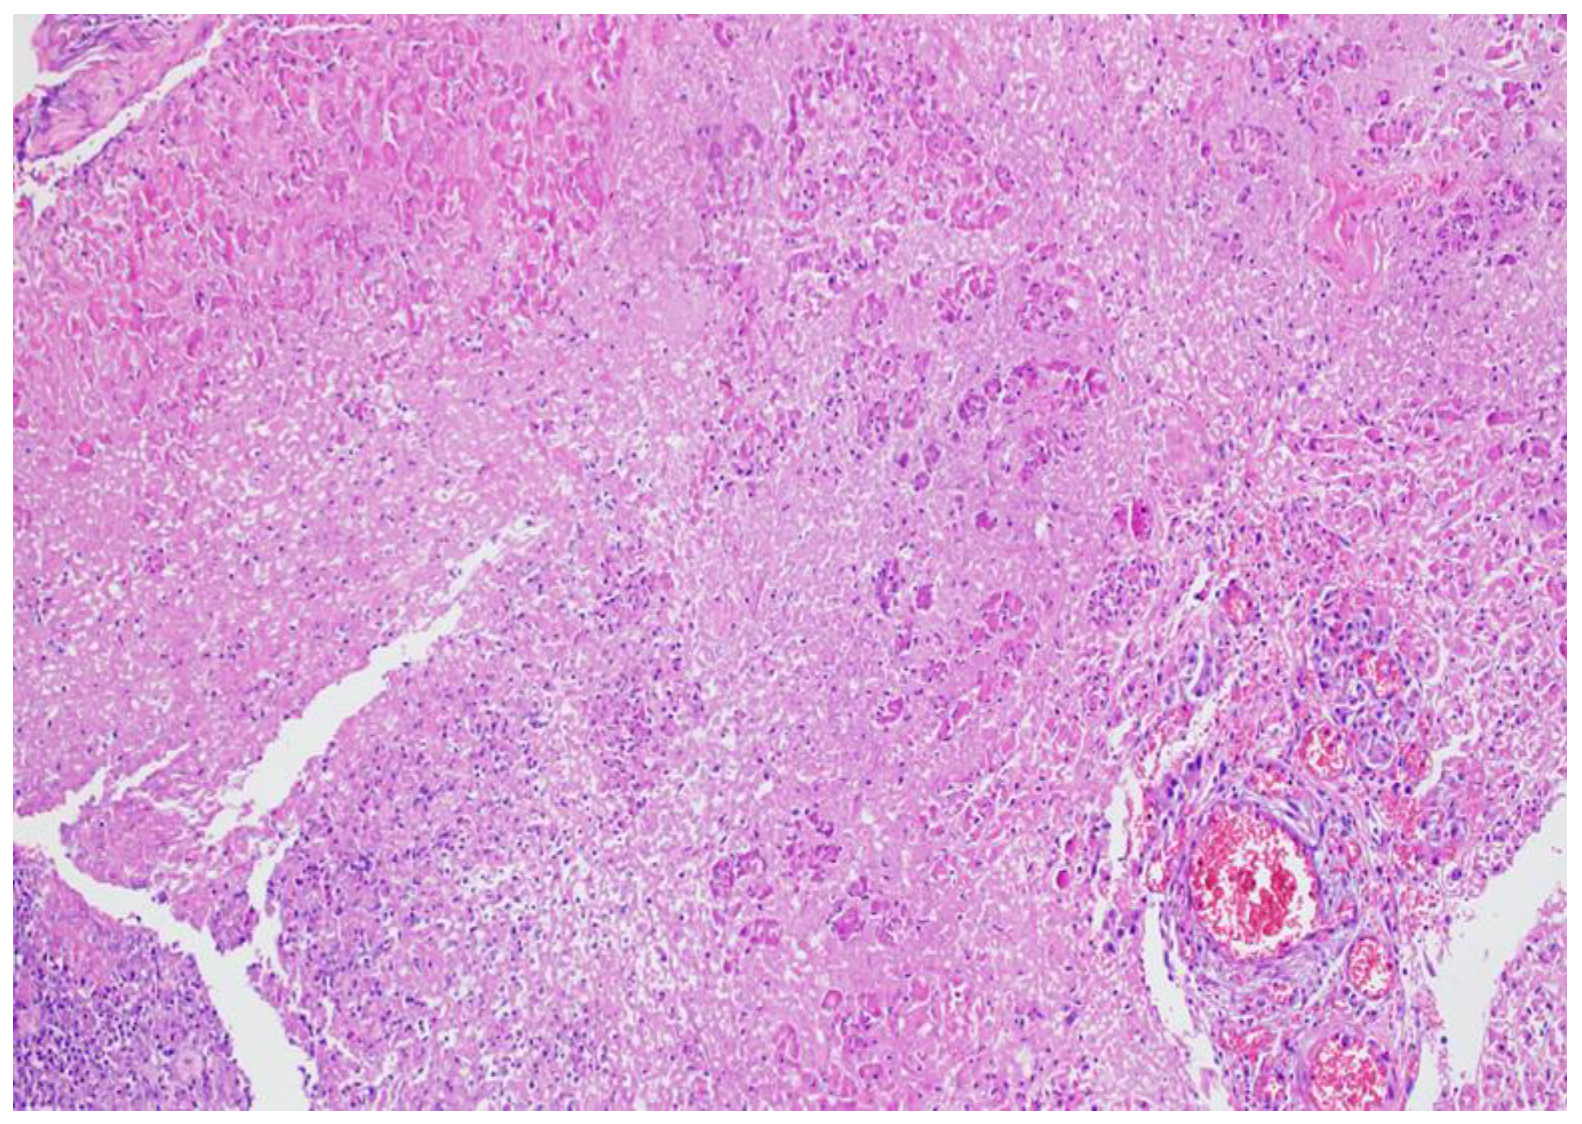

4. Histopathology of Acute Pancreatitis